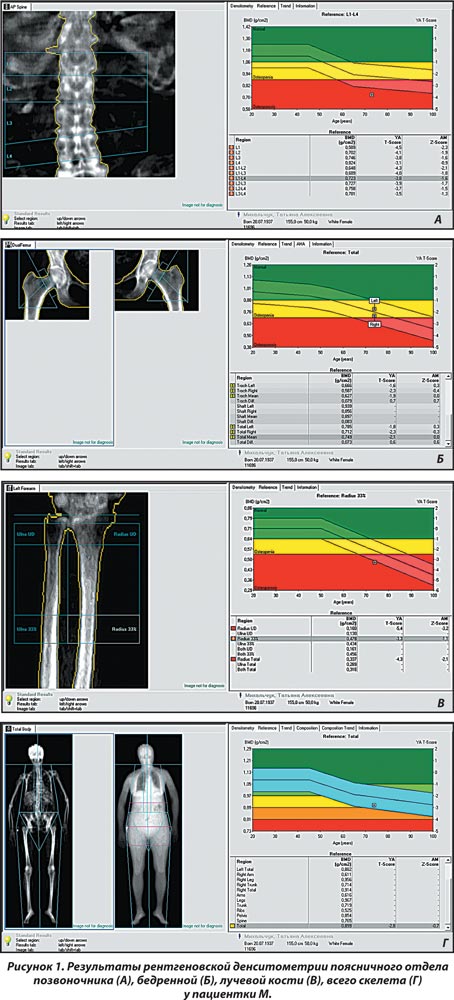

Результаты двухфотонной рентгеновской абсорбциометрии (рис. 1): Т-критерий составил на уровне позвоночника — –4,5 SD; бедренной кости — –2,1; лучевой кости — –2,1; всего скелета — –2,8 SD. По данным рентгенморфометрического исследования позвоночника, деформации тел позвонков не выявлено.

Таким образом, по данным рентгеновской денситометрии установлен системный остеопороз, однако изменения в биохимическом анализе крови вызывают необходимость дополнительных исследований (рентгенографическое исследование, консультации других специалистов и прочее для исключения диагноза вторичного остеопороза).

С учетом жалоб больной, анамнеза заболевания и жизни, данных объективного статуса и дополнительных методов исследования был верифицирован клинический диагноз: вторичный системный остеопороз. Детальный сбор анамнеза выявил множество причин, влияющих на метаболизм костной ткани в различные периоды жизни конкретной больной, — гипопластическая анемия, прием глюкокортикоидов, узловой зоб с гипертиреозом, гиперпаратиреоз, и, наконец, дефицит эстрогенов в постменопаузе. Поскольку проведение рентгеновской абсорбциометрии проводилось пациентке впервые в клинике, чрезвычайно сложно определить, какая из причин была наиболее значимой для потери костной массы у конкретной пациентки. Однако наличие определенного симптомокомплекса жалоб (судороги, ноющие боли в длинных костях) и полученных результатов инструментального (системный остеопороз) и лабораторного обследования (гипокальциемия, гипомагниемия, гиперфосфатемия, низкий уровень витамина D) обусловливает выбор назначаемого лечения.